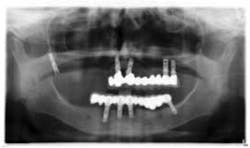

An 81-year-old female with stent placement 10 years ago taking no medications presented with a chief complaint that her old prosthesis broke, and she cannot chew and function. She had a previous bridge consisting of an implant in the No. 1 site combined with the natural teeth and implants in the 8, 9, 14, 15. No. 8, 9 implants were malpositioned with a 35-degree angle and significant mucogingival defects.

Various treatment options were explained to the patient, and a treatment plan consisting of Coldwell-Luc external sinus lift with bilateral block placement in area 5 to 7 and 10 to 12 was agreed upon.

Under local anesthesia, a full thickness flap was elevated from the upper right to upper left posterior segments. Using a piezoelectric handpiece, a buccal window hinge osteotomy was elevated in the maxillary right posterior region. A mixture of DFDBA, anorganic bovine bone, and PRF was placed. A collagen membrane was used to cover the buccal window. Simultaneously, two puros J-block allografts were secured in the 5 to 7 and 10 to 12 region with stainless steel screws (1.6 x 8 mm screws). A mixture of DFDBA, anorganic bovine bone and PRF was placed over each area and covered with PRF sheet and a collagen membrane. Primary closure was obtained with CV-5 Goretex sutures. Healing was uneventful. After six months of healing, six straight implants were placed in sites 3, 4, 5, 6, 11, and 12. Healing abutments were placed at stage I. Healing was uneventful. After four months of healing, six custom abutments were fabricated by his dentist and cover screws were placed on implants 8 and 9 and converted into pontics.

Case 2: Sinus lift, bone graft, PRP, and after healing implant placement